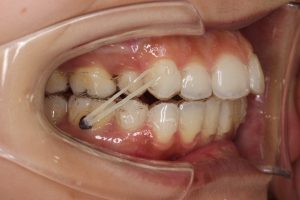

そして、ゴムかけを再開することになりました。

以前はこのように、

ゴムをかけるために片方には銀のボタンをつけていましたが、

今回はマウスピースとマウスピースでゴムかけをします。

(マウスピースをよーく見るとひっかけがあるんです!!)

ひっかけのある歯にはアタッチメントもあるのでしっかりかけられます。

こんな感じです。

白っぽい膨らみ=アタッチメントです。

上の写真は、アタッチメントをつけてマウスピースを装着している状態です。

(アタッチメントはこのような時にも役に立つんですね!)